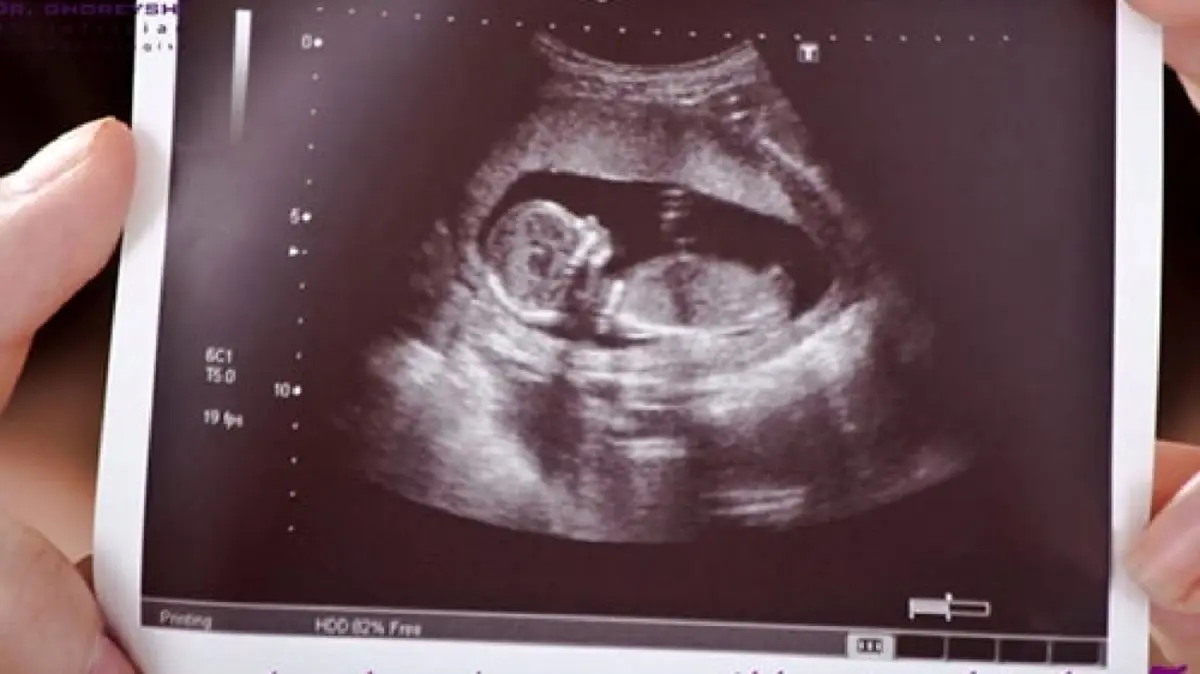

بیمه شدن هزینه سونوگرافی بارداری

رکنا: مسئول دبیرخانه قرارگاه سلامت و جوانی جمعیت وزارت بهداشت، درمان و آموزش پزشکی گفت: هزینه آزمایشهای تصویربرداری های مربوط به مادر و جنین تحت پوشش بیمه پایه و تکمیلی قرار خواهد گرفت.

به گزارش رکنا، صابر جباری افزود: بر مبنای تبصره ۴ ماده ۵۳ هزینه آزمایشهای تصویر برداری های مربوط به مادر و جنین از جمله انواع سونوگرافی بارداری تحت پوشش بیمه پایه و تکمیلی قرار خواهد داشت و از این جهت قانون گذار دغدغه هزینه های تشخیصی و درمانی برای همه مردم به ویژه برای خانواده های محروم و بی بضاعت را به خوبی دیده است.